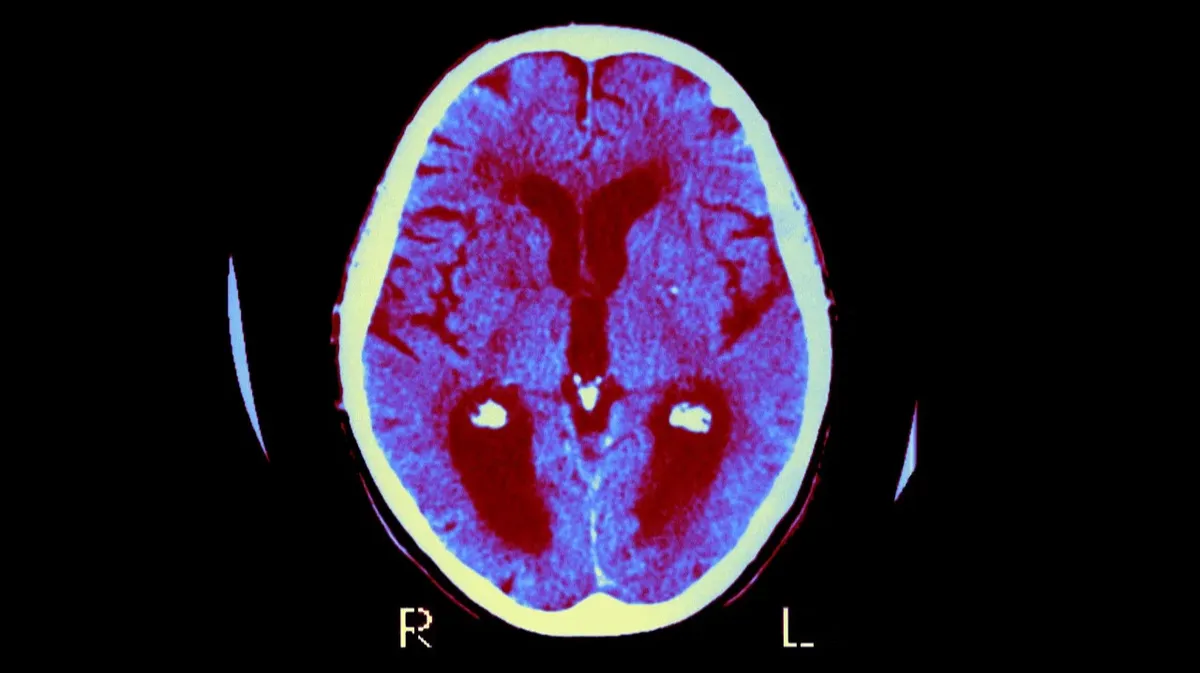

Мозг пациента с болезнью Альцгеймера. Осевой вид в разрезе. Фото: BSIP / UIG / Getty Images